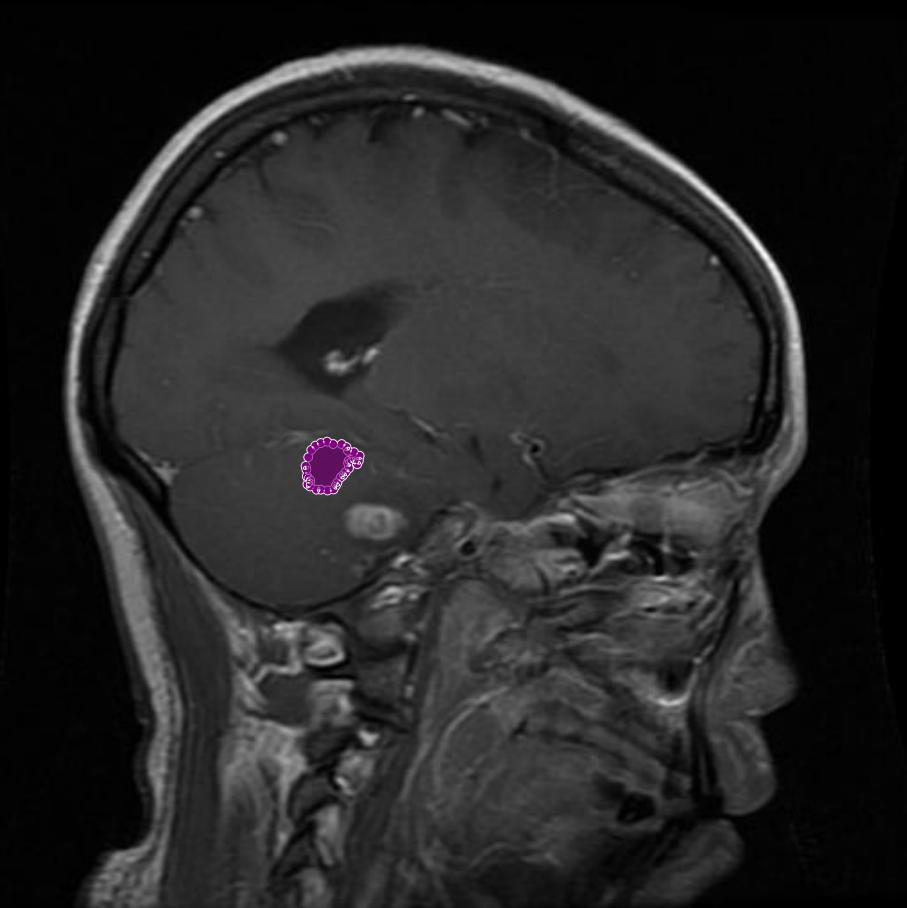

Figure 7: Samples of partial-region underannotations. The purple area indicates regions that were initially marked as non-tumorous but were later identified by the radiologist and physician as tumorous.

Conversely, there were cases where genuine tumor regions had been overlooked during the initial annotation process. With input from the Physician and radiologist, these missing regions were added to the annotations, ensuring that the masks comprehensively captured all tumor areas. Figure 7 demonstrates an example of such an adjustment, where previously unannotated tumor segments were correctly incorporated into the final mask.

Achieving accurate tumor segmentation required a meticulous process of iterative reviews and refinements, conducted in close collaboration with a physician and a radiologist. This collaborative effort was crucial in ensuring that the final annotations accurately reflected the true tumor boundaries, minimizing errors and improving the overall quality of the dataset. In some cases, regions initially annotated as tumors were later identified by physician and radiologist as non-tumorous. These corrections were essential to avoid false positives that could mislead model training. An example of such a case is shown in Figure 5, where an area initially believed to be a tumor was excluded from the final annotation after expert review. In other instances, certain areas that were mistakenly included as part of the tumor region were refined based on radiologist and physician feedback. These areas, though visually similar to tumor tissue, were determined to be non-tumorous upon closer examination. As illustrated in Figure 6, the removal of these incorrect segments resulted in more precise tumor masks and enhanced the reliability of the dataset. Conversely, there were cases where genuine tumor regions had been overlooked during the initial annotation process. With input from the Physician and radiologist, these missing regions were added to the annotations, ensuring that the masks comprehensively captured all tumor areas. Figure 7 demonstrates an example of such an adjustment, where previously unannotated tumor segments were correctly incorporated into the final mask.Challenges of non-tumorous Conditions